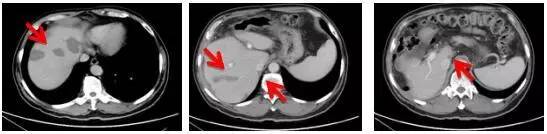

患者治疗前肝转移情况

经过靶向治疗联合化疗,患者病灶缩小

2015.7.3

2015.9.4

2015.12.4